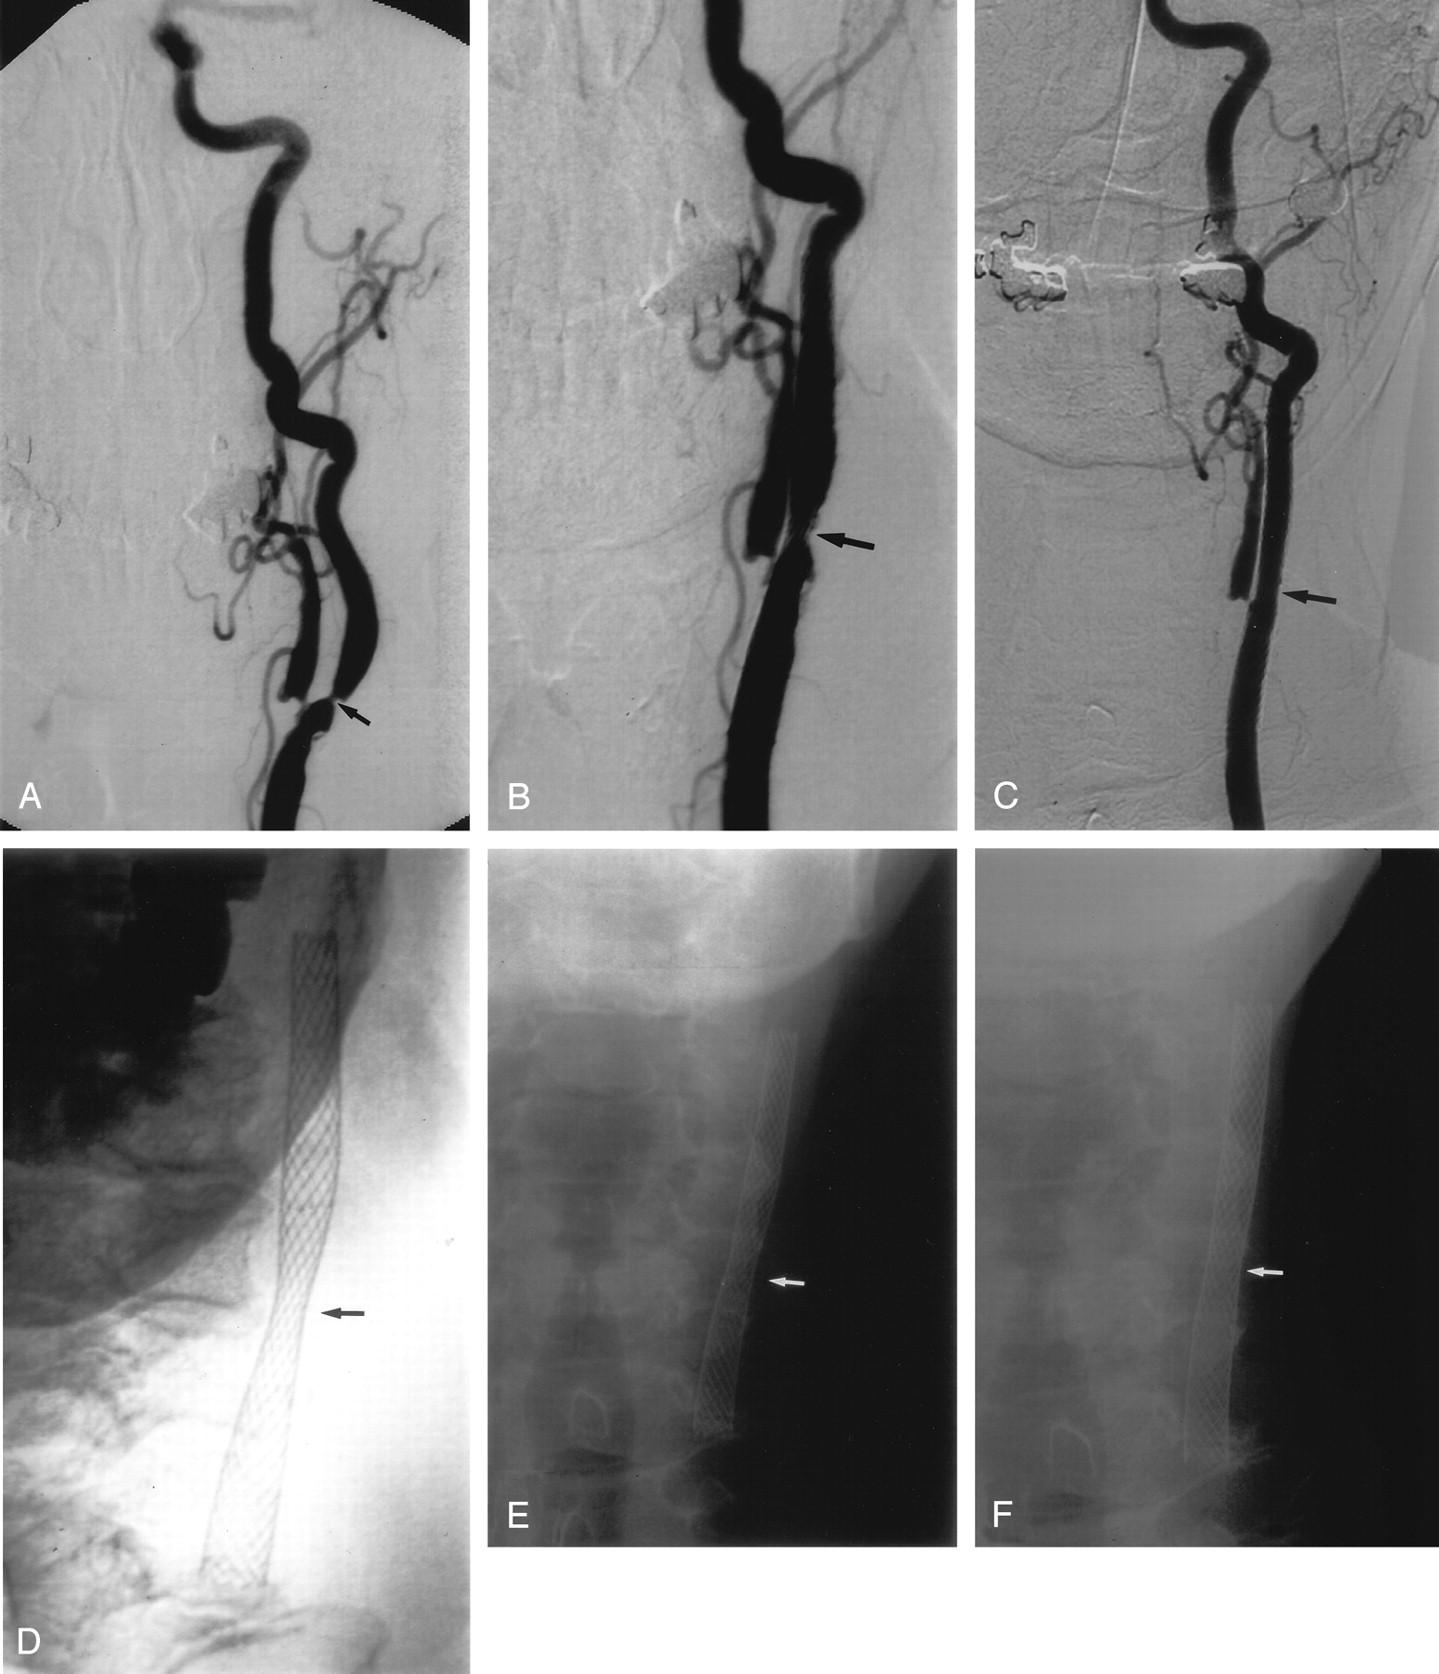

Eleven patients had repeat sonography during the first week after treatment. The mean peak systolic velocity (PSV) fell from 461 cm/s to 275 cm/s and the average ICA/CCA ratio from 7.3 to 3.4. Subsequent follow-up was done in 20 patients, excluding the patient in whom balloon predilatation was required. Follow-up ranged from 1 to 44 months, with an average of 20 months (Figs 4 and 5). Mean PSV at last follow-up in all patients was 164 cm/s (median, 118 cm/s; range, 60–628 cm/s). Mean follow-up ICA/CCA ratio was 2.2 (median, 1.7; range, 0.8–7.9). All had velocities at or below 180 cm/s, except for three patients. One of these three had contralateral ICA occlusion, which would elevate velocities due to increased collateral flow, and this was confirmed by color Doppler, which showed that the degree of stenosis was mild. The second patient had a transient ischemic attack with recurrent severe stenosis at 16 months and continues to be followed. The third patient, by far the worst result in the series, had an unusually marked degree of plaque calcification. Her velocities and ratios remained high—628 cm/s and 7.9, respectively—out to 1 year of follow-up. The degree of plaque calcification prevented stent expansion (Fig 6). She remained free of further episodes of ischemia for 1.5 years, at which time her stenosis progressed to complete angiographic occlusion, with no new evidence of stroke on MR imaging.

A, Right lateral CCA DSA, showing a severe stenosis of the proximal ICA, measuring approximately 80%.

B, Repeat lateral DSA, poststenting alone, showing reduction of the stenosis to approximately 63%.

C, D, and E, Conventional AP radiographs of the neck immediately poststenting (C), 5 months (D), and 8 months (E) poststenting. There has been no further expansion of the stent over 8 months. Note the prominent, focal plaque calcification (arrows).

Range of Luminal Expansion in the Stent

The mean degree of luminal expansion on the immediate postprocedure angiogram was 35% (median, 35%; range, 9–70%). Subsequently, between the first postprocedural radiograph and the final follow-up study, the mean luminal expansion was 31% (median, 33%; range, 7–53%). The effect of the stent on the atheromatous plaque could be categorized into four groups (Fig 7): (1) a striking immediate expansion much greater than any delayed response (five patients), (2) little immediate response but marked delayed expansion (two patients), (3) relatively equal immediate and delayed expansion which in combination resulted in a satisfactory dilatation (12 patients), and (4) neither an effective immediate nor a delayed response (one patient). The three patients in groups 2 and 4 showed only a minimal immediate response to stent placement (9%, 13%, and 18% luminal expansion, respectively). Of these, the two in group 2 had improved to 20% and 18% residual stent stenosis by 2 and 3 months, respectively. The third patient (group 4) with a severely calcified plaque had minimal delayed expansion and the stent was occluded at 18-month follow-up.